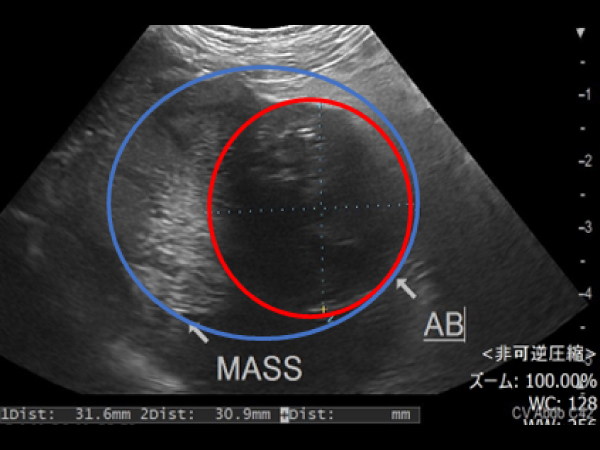

外側左葉に63.3㎜×61.5㎜の肝臓腫瘍が認められ細胞診にて肝細胞癌と診断されたました。 摘出も可能でしたが高齢であり、過去に何度か開腹手術もしており、甲状腺がんの摘出も同時に手術を行うため負担の少なさを考慮しフュージョンイメージングを用いてアブレーションを実施しました。 超音波ガイド下で肝臓腫瘍の周囲に生理食塩水を満たすことで周囲の組織を熱で損傷することなく安全に実施が可能です。 術後の経過も良好で次の日に退院しました。

アブレーション実施の様子

超音波を当てながらアンテナ(青矢頭)を挿入している

アブレーション実施中の超音波画像

アンテナ(青矢頭)と焼灼されているところ(赤丸)